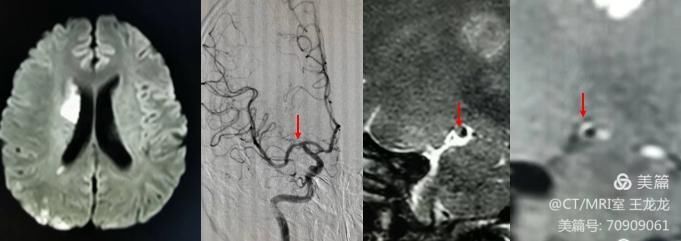

30岁脑梗患者,大脑中动脉硬化性斑块合并炎症

2、可以评估责任血管斑块可能存在的危险因素(斑块内出血、纤维帽不连续、斑块炎性反应及斑块内大脂质核)。